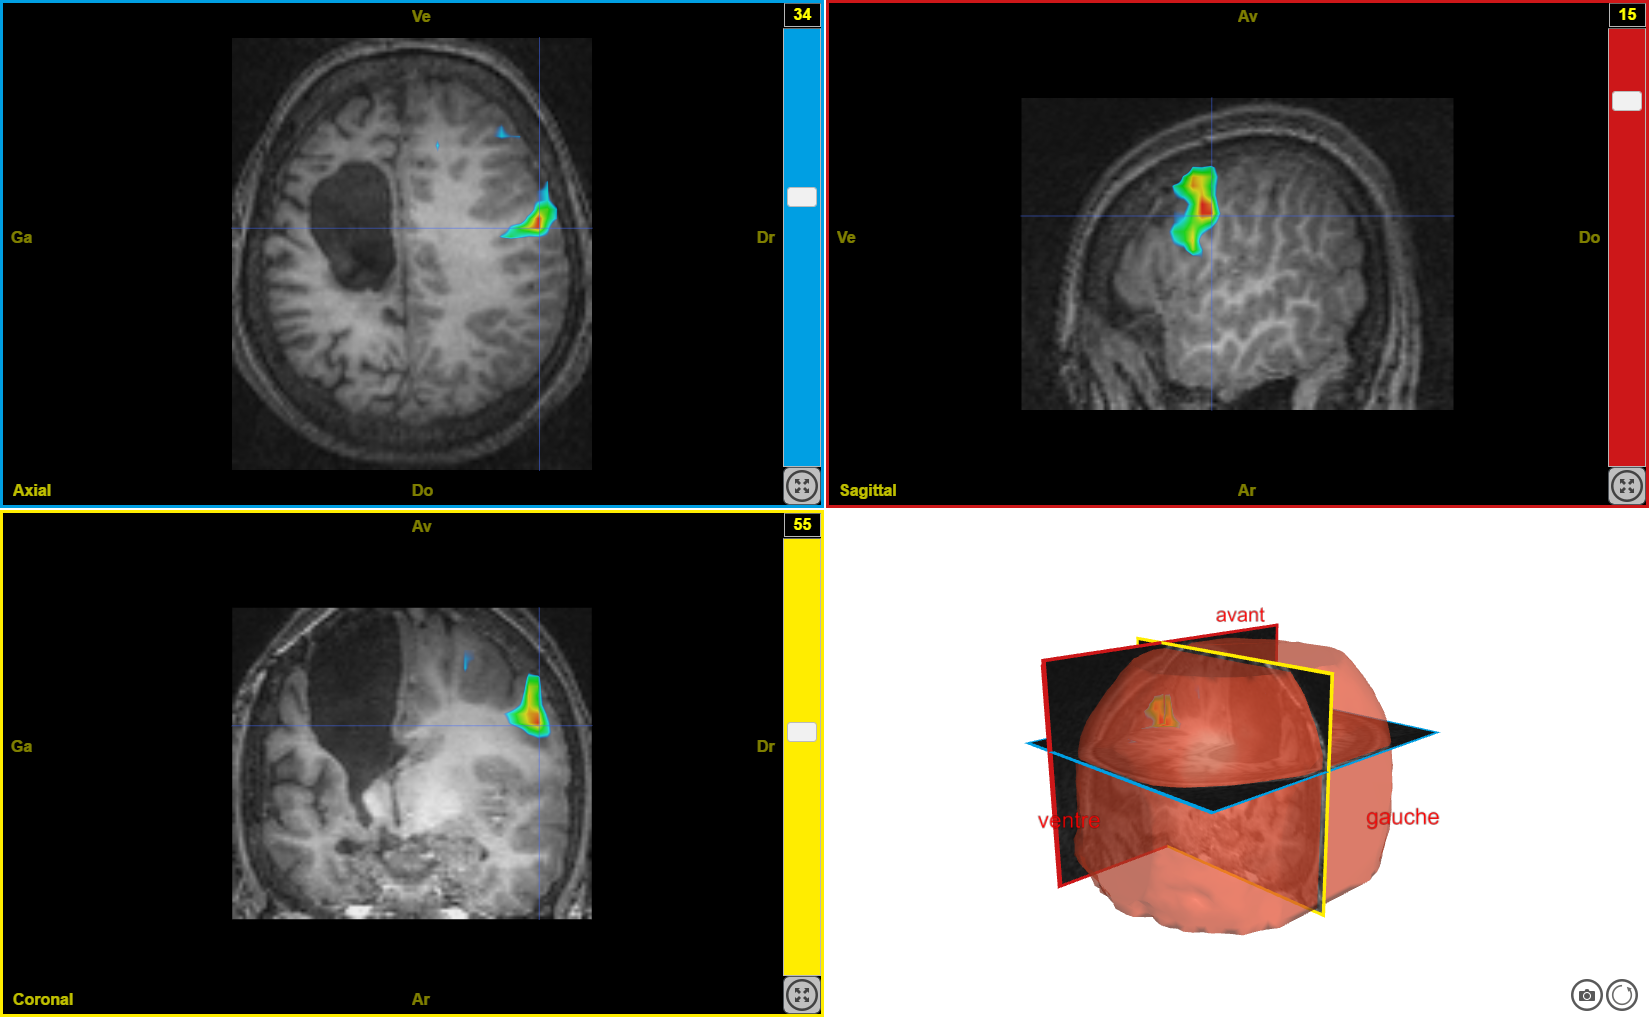

plasti2

Image dans sa taille originale :

409 ko

Ancien logiciel : EduAnatomist et Neuropeda

Informations sur les images AnaPeda

Exemple de lien direct vers EduAnat 2 en ligne